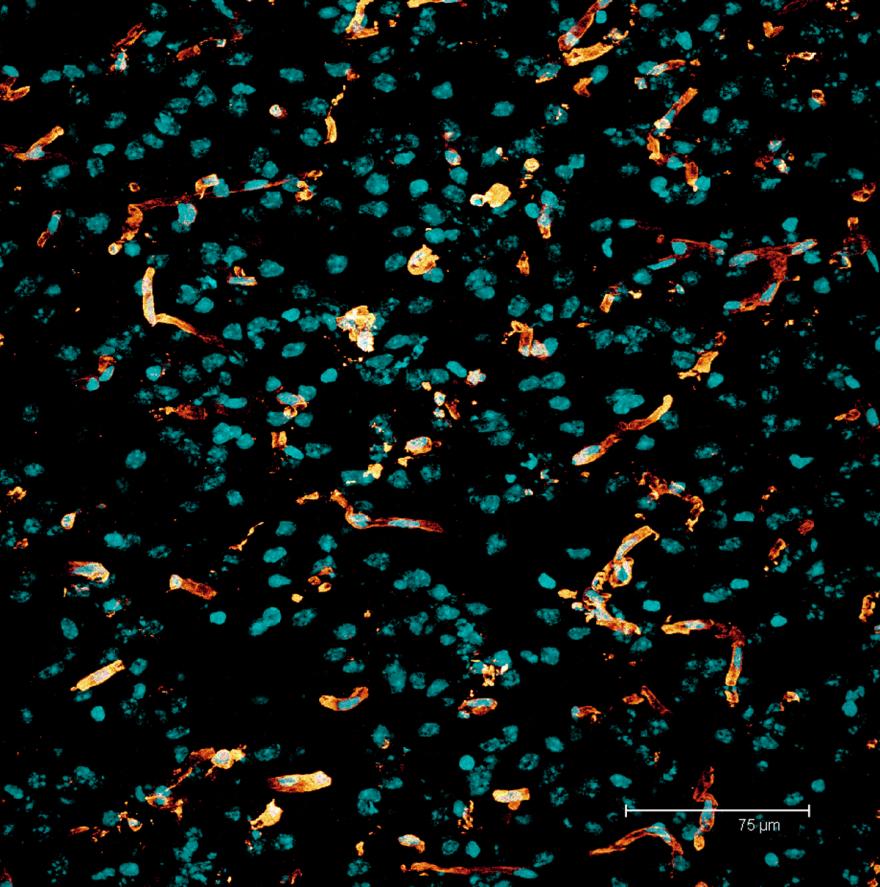

Maximum projection image of a rat brain section. Nuclei stained with Draq-5 (cyan). Vasculature stained with anti-laminin (glow). Depth of section 12.21 µm.